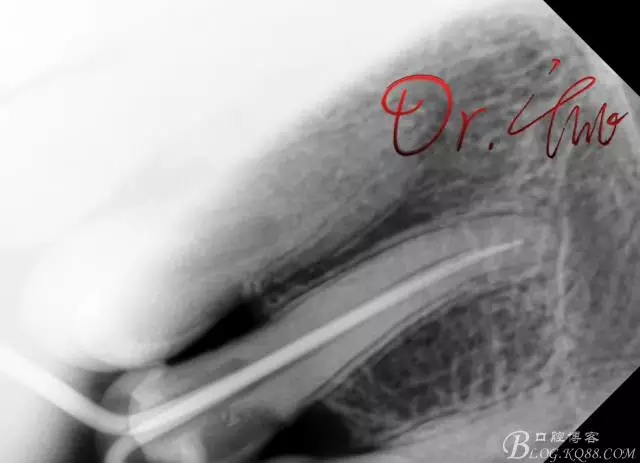

試主尖,近中頰側(cè)再次拍片查看臺階位置及確定長度

640.webp (8).jpg

試主尖,近中頰側(cè)試主尖,此時手用銼02錐度的已擴到30號,可以明顯感覺到臺階位置,挫預(yù)彎后找好正確位置可順利到達根尖,但是機用銼就是下不去,也是郁悶